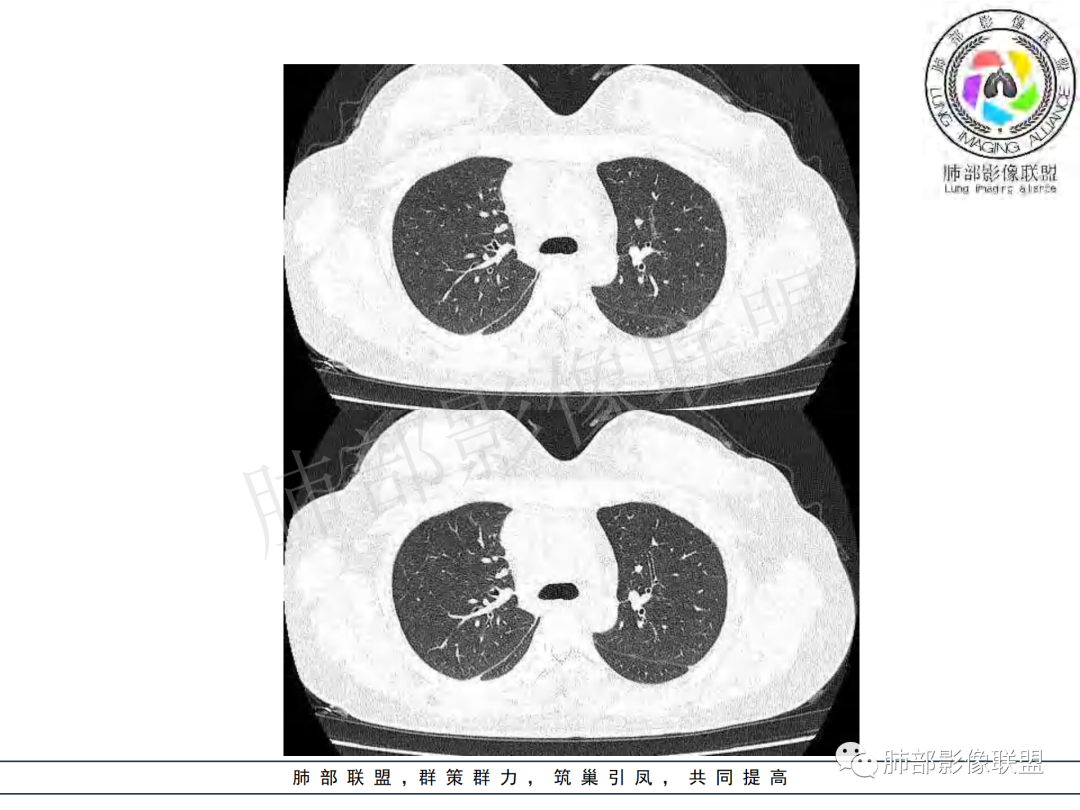

右肺肺门旁肿块,右肺中间段支气管腔内结节,增强强化不均;纵隔多发淋巴结环形强化,右侧少量胸腔积液,临床发热入院,考虑结核,鉴别肿瘤。

右肺门增大,远端花花草草不明显,支气管管壁增厚,纵隔淋巴结环形强化,年龄,病程,考虑炎性病变,结核可能,有个层面支气管截断,有强化,鉴别粘表。

纵隔多组及右侧肺门多发肿大淋巴结,部分融合,不均匀强化,内见斑片状坏死区及环状强化,后者坏死边界尚清晰,肺门区肿大淋巴结与肺组织边界不清,年轻女性,8个月病史,发热首发症状,考虑淋巴结核并向肺内侵及(破溃?),鉴别淋巴瘤

女,20,病程长达8月,发热、胸痛、右侧胸腔积液病史。胸部CT:右肺门旁不规则肿块影,右中间支气管腔内结节,纵隔多发淋巴结肿大;强化不均匀,灶性坏死灶,环形强化;右侧少量胸腔积液并局部肉芽肿样突起。年轻女性,长病程,多部位,考虑慢性炎症,结核?鉴别肿瘤。

年轻女性,慢性病程,发热、胸痛。右肺门旁不规则肿块影,纵隔多发淋巴结肿大;强化不均匀,环形强化;右侧少量胸腔积液;首先考虑结核,鉴别肿瘤,结节病。

慢性病程,前纵隔右肺门旁多发淋巴结肿大;强化不均匀,环形强化;右侧少量胸腔积液;考虑结核,鉴别结节病。

年轻女性,右肺门区病变伴纵隔淋巴结肿大,强化显示环形强化,考虑结核可能性大

本例患者,年轻女性,慢性病程,多次抗感染治疗效果不佳,实验室检查示白细胞及中性粒细胞不高,不支持普通细菌感染,虽然肺泡灌洗液X-Pert检测阴性,结合患者胸部CT结核感染亦不能排除,胸部CT主要表现为右侧肺门及纵隔淋巴结肿大,仔细观察不难发现右中间支气管内新生物凸向管腔内,增强扫描,右肺门(10R)及纵隔淋巴结(2R,4R)明显不均匀强化,内部呈不规则低密度无强化区,被周边高强化区包绕(环形强化)的特点,首先应当想到纵隔淋巴结结核诊断。淋巴结分布亦不符合肺部恶性肿瘤迁徙途径。